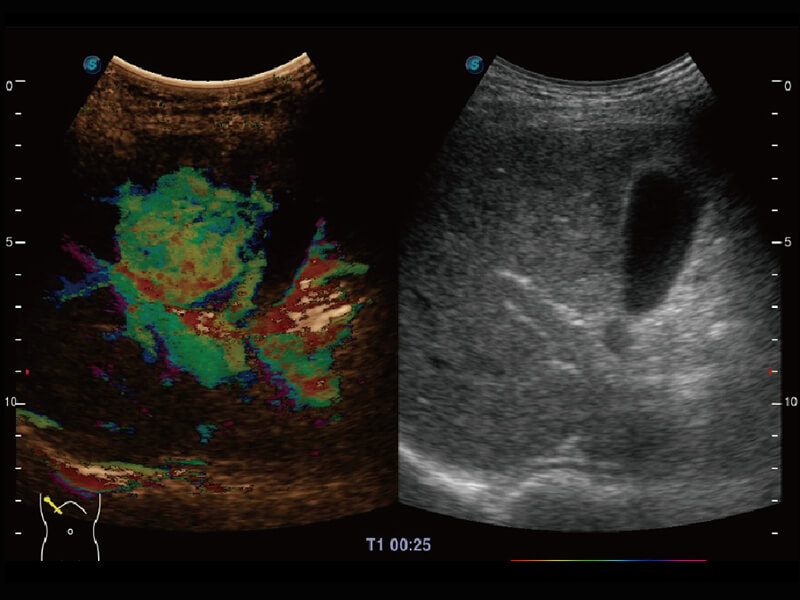

彩色多普勒超声诊断系统

性能优异的硬件架构,极大提升超声系统的运行效率和数据处理能力。相比以往超声成像系统,Wis+平台为您带来极快的响应速度和成像帧频,提升检查流畅度。

S60探头工艺,从前端信号处理每一个环节采集无损声学数据,真实还原组织原貌,再现解剖细节。

超宽频带技术,为容积成像带来优质的二维图像基础,为您呈现丰富的结构细节,栩栩如生地展示宝宝的宫内形态以及各种组织的立体结构。